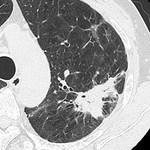

[画像診断]癌性リンパ管症のHRCT所見について 2010-09-22

[画像診断]器質化肺炎のHRCT所見について 2010-09-21